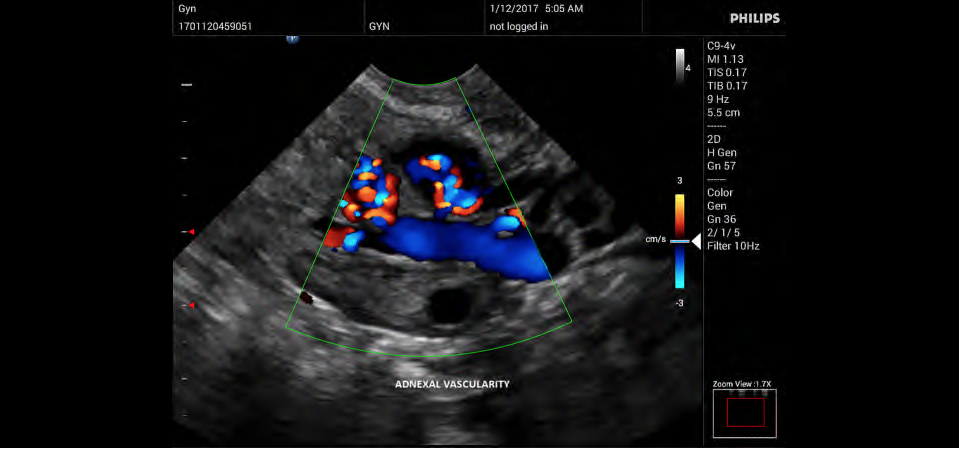

Philips InnoSight

Philips InnoSight увеличивает возможности сканирования во множестве мест оказания медицинских услуг. Благодаря данному УЗИ аппарату врачи могут не сомневаться в быстром выполнении обычных ультразвуковых сканирований во врачебном кабинете, клинике или больнице.

InnoSight позволяет перенести ультразвуковую диагностику непосредственно туда, где пациенту оказывается медицинская помощь, что повышает мобильность врачей. Этот компактный и легкий ультразвуковой аппарат позволяет чаще использовать возможности ультразвуковой диагностики и предоставляет широкий набор технологий для проведения углубленных исследований — программные пакеты для специализированного анализа, функции аннотирования и наборы готовых настроек для различных типов тканей.

Эргономичная система с высококачественными широкополосными датчиками Philips помогает повысить клиническую надежность результатов исследования и уровень оказания медицинских услуг. Аппарат можно перемещать вручную или с помощью тележки.

• Акушерство и гинекология;

• Цветное допплеровское картирование

• Направленный энергетический допплеровский режим: Дополнительно к возможностям визуализации сосудов в стандартном энергетическом режиме добавляется информация о направлении. Этот режим полезен для визуализации мелких сосудов в качестве замены цветного допплеровского картирования.

• Конвексный УЗИ датчик Philips C9-4v